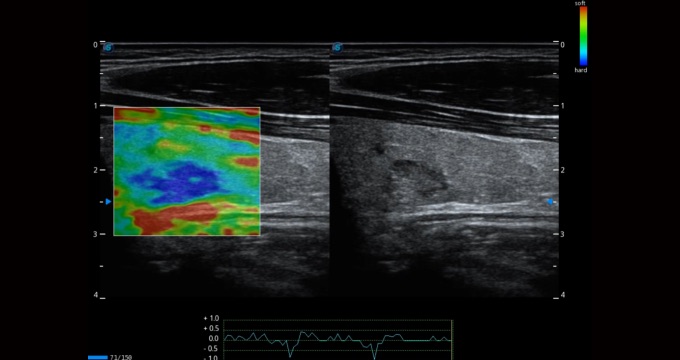

• 弹性成像

弹性成像支持多把探头,满足更多的临床应用。无需高频度外力作用可真实反映组织的形变,具有良好的重复性,更早地洞察潜在的病理学特征。